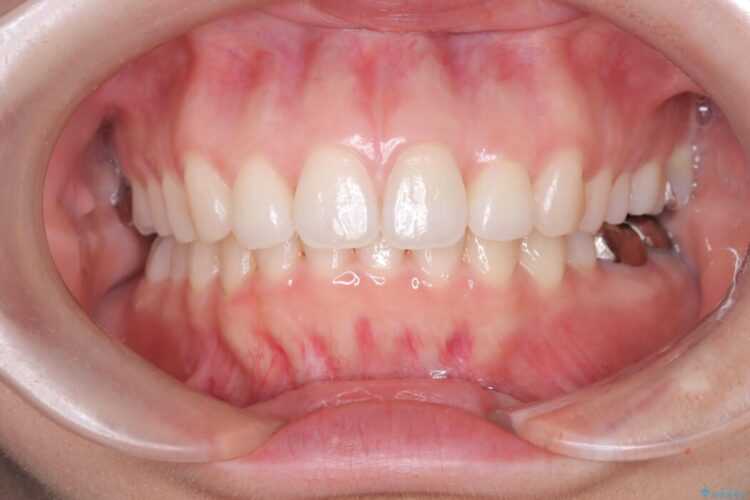

前歯が前方へ出ていることを気にされて来院されました。 横からの画像を見ると分かりやすく前へ出ている(上顎前突)のが確認できます。

噛み合わせが良くなり、きれいな歯列となったことで患者様に喜んでいただけました。